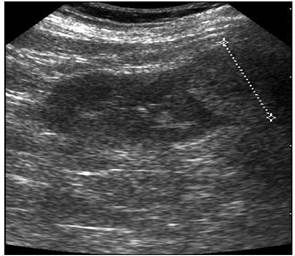

Понимание кавернозного туберкулеза почки

Раздел: Мудрость в деталях